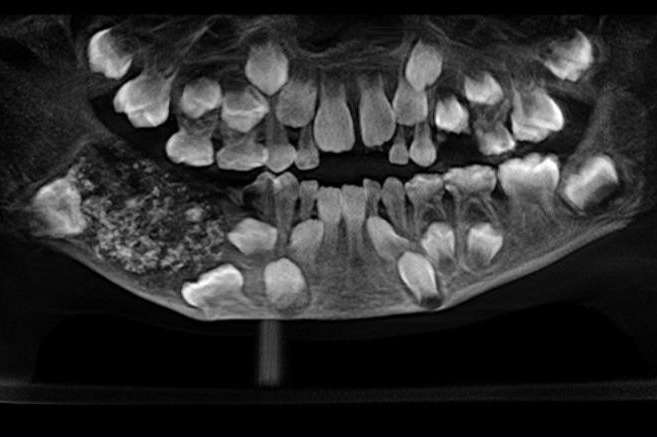

Мальчик пожаловался на сильную боль в челюсти и попал в больницу. Рентген показал, что в правой части нижней челюсти у ребенка образовалось 526 зубов.

Все они скопились в одной полости в нижней челюсти справа. Размер каждого зуба составлял от 0,1 до 15 миллиметров. Даже у самого маленького образования была собственная коронка, корень и эмалевое покрытие, подтверждающие, что это действительно зуб, сообщил CNN один из врачей.

Врачи диагностировали у него смешанную сложную одонтому – это доброкачественная опухоль, состоящая из элементов зубных тканей. Чем она вызвана, неизвестно. Врачи не исключают генетический фактор и экологию (например, негативное влияние могла оказать повышенная радиация).